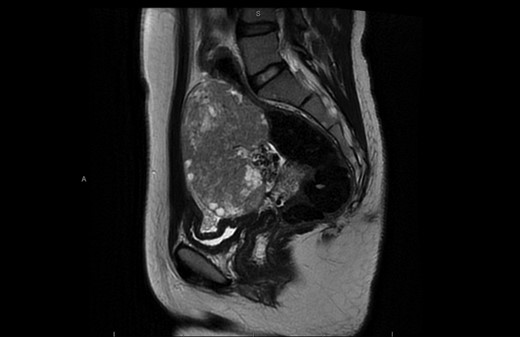

A 23-year-old female patient was referred to our institution because of a history of vague abdominal pain associated with significant distension. She reported no other symptoms. Clinical examination revealed a large lower abdominal and right sided mass which was thought to be arising from the right adnexa. Full laboratory work-up showed no significant changes. Abdominal CT scan showed a large, right sided and heterogeneous adnexal mass (Fig. 1).

CT scan showing large right sided heterogeneous lesion 10 × 10 × 7 cm3.